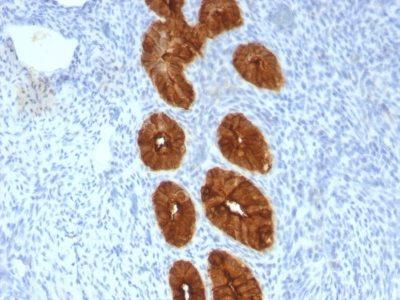

This MAb recognizes full-length MUC1 in a glycosylation-independent manner and can bind to the fully glycosylated protein. The dominant epitope of this MAb is APDTR in the VNTR region. It reacts with the core peptide of the MUC1 protein, which is a member of a family of mucin glycoproteins that are characterized by high carbohydrate content, O-linked oligosaccharides, high molecular weight (>200 kDa) and an amino acid composition rich in serine, threonine, proline and glycine. The core protein contains a domain of 20 amino-acid tandem repeats that functions as multiple epitopes for the MAb. Incomplete glycosylation of some tumor-associated mucins may lead to variable unmasking of the multiple peptide epitopes leading to the observed differences in staining intensity between normal and malignant tissues. This MAb reacts with both normal and malignant epithelia of various tissues including breast and colon.Primary antibodies are available purified, or with a selection of fluorescent CF® Dyes and other labels. CF® Dyes offer exceptional brightness and photostability. Note: Conjugates of blue fluorescent dyes like CF®405S and CF®405M are not recommended for detecting low abundance targets, because blue dyes have lower fluorescence and can give higher non-specific background than other dye colors.

MCF-7 or MDA-231 cells. Breast, colon, ovarian, endometrial carcinoma.

Immunohistology formalin-paraffin 0.25-0.5 ug/mL|Staining of formalin-fixed tissues requires boiling tissue sections in 10 mM citrate buffer, pH 6.0, for 10-20 min followed by cooling at RT for 20 minutes|Flow Cytometry 0.5-1 ug/million cells/0.1 mL|Immunofluorescence 1-2 ug/mL|Optimal dilution for a specific application should be determined by user